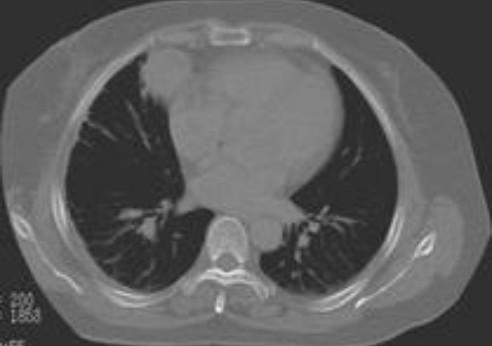

春节前夕吴小姐肚子很痛,到深圳怡康产医院用四维彩超检查发现,右侧附件中有混合回声区,并可触摸到排球大小的包块。手术中,该院妇产专家发现,吴小姐长了一个畸胎瘤,且有一定年数,而从畸胎瘤中拿出的东西令人不寒而栗:骨骼、头皮、脂肪及几绺头发和25颗成人牙齿。

而卵巢畸胎瘤与妊娠无关,发展成“畸胎瘤”的生殖细胞并非受精卵,无法发育成胎儿,只能形成器官组织。因为生殖细胞中含有人体外胚叶、中胚叶和内胚叶三种组织成分,所以瘤子里会有毛发、皮肤、牙齿、骨片等外胚叶组织。